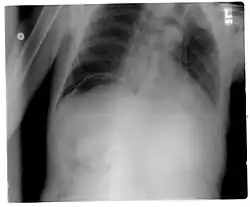

Pneumopéritoine (Rayons X).